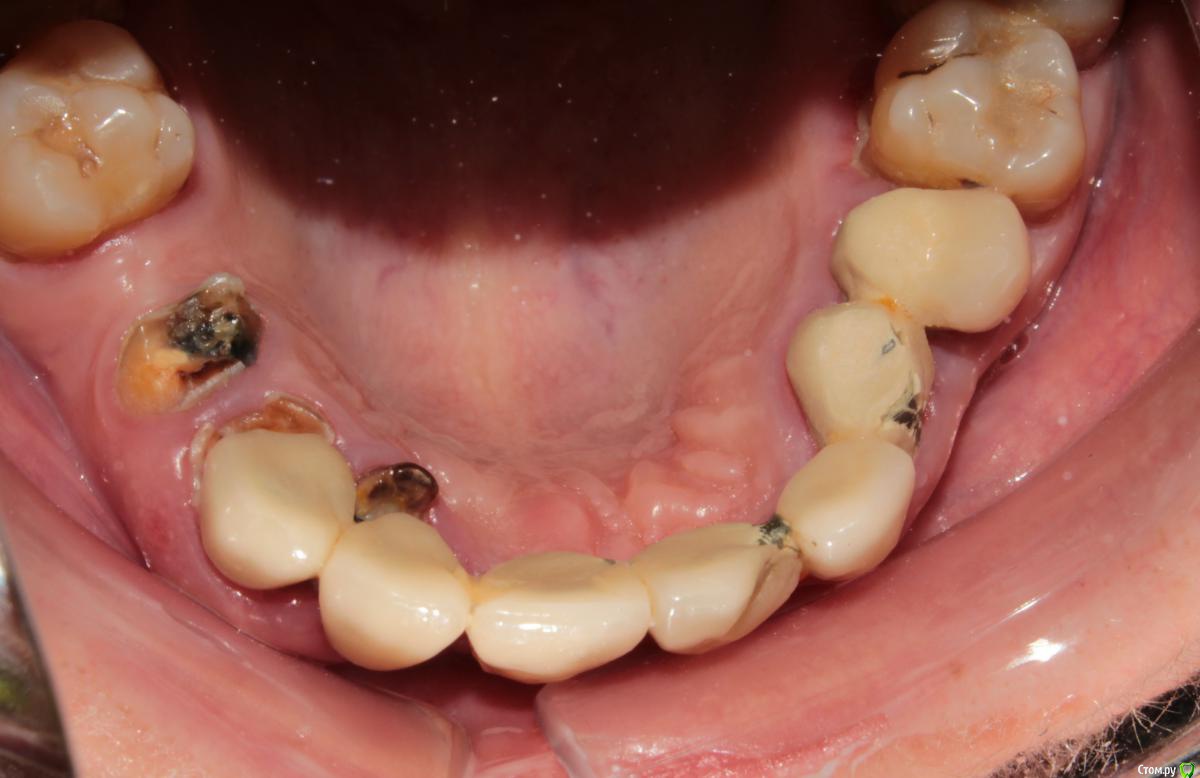

Витторио Орлионе Опубликовано 12 декабря, 2016 Поделиться Опубликовано 12 декабря, 2016 Здравствуйте, уважаемые форумчане. Поделитесь пожалуйста своим мнением и опытом вот по такому случаю: пациентка 40 лет обратилась с жалобами на подвижность мостовидного протеза и хочет реабилитации. Импланты позволить себе не может и очень хочет несъёмную конструкцию. Пожалуй самый главный вопрос: что целесообразней: перелечить те из опорных зубов, которые ещё можно сохранить и покрыть их коронками или удалить все корешки и восстановить их уже в съёмном протезе? Возможно ли использовать эти корни для лучшей фиксации протеза во рту и как? Ссылка на комментарий

Витторио Орлионе Опубликовано 13 декабря, 2016 Автор Поделиться Опубликовано 13 декабря, 2016 Сегодня мостик сняли и вот что под ним было. А что касается верхних моляров, то 2.8 весь в кариесе, 2.7 уже с 1 степенью подвижности, и выдвинулись они там мм на 3 что в 1м, что во 2м сегменте.пожалуй стоит задуматься о пспп. Ссылка на комментарий

StomV Опубликовано 14 декабря, 2016 Поделиться Опубликовано 14 декабря, 2016 Сегодня мостик сняли и вот что под ним было. А что касается верхних моляров, то 2.8 весь в кариесе, 2.7 уже с 1 степенью подвижности, и выдвинулись они там мм на 3 что в 1м, что во 2м сегменте.пожалуй стоит задуматься о пспп. Вот вопрос о сохранении отпал сам собой. Ссылка на комментарий